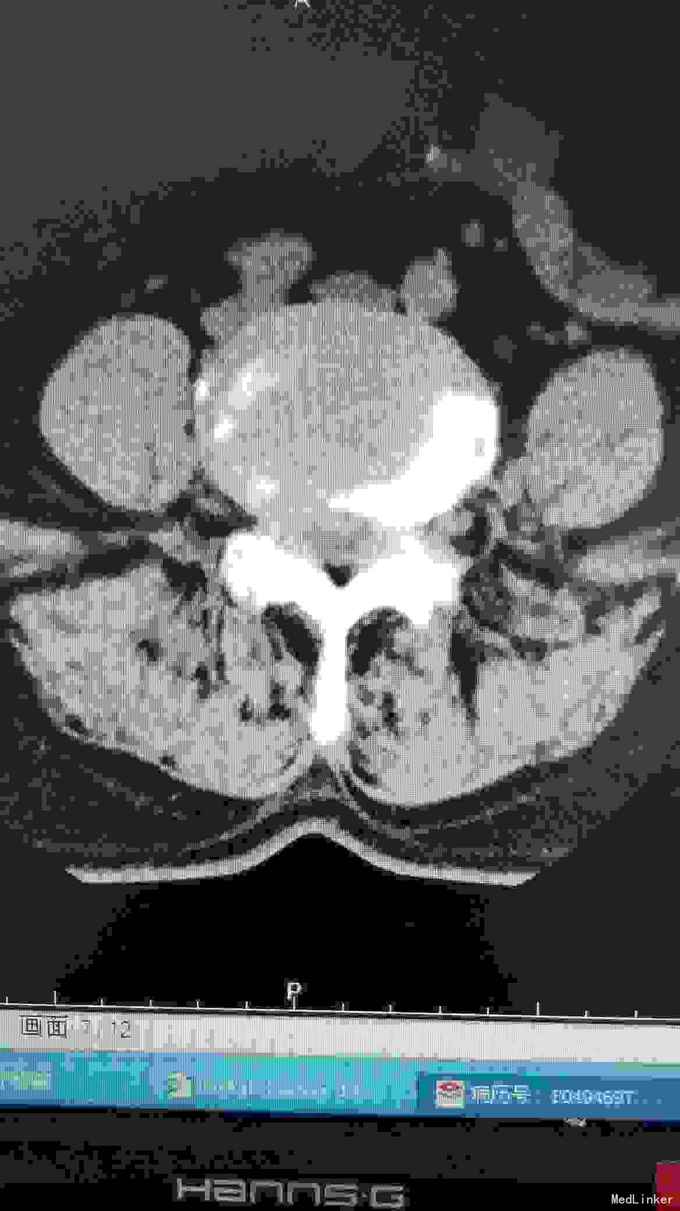

腰椎影像检查提示椎间盘突出,椎管狭窄,退变侧弯。

诊断腰椎间盘突出症,腰椎管狭窄症,腰椎退变性侧弯。 在全麻下行腰椎固定,减压,畸形矫正融合术。